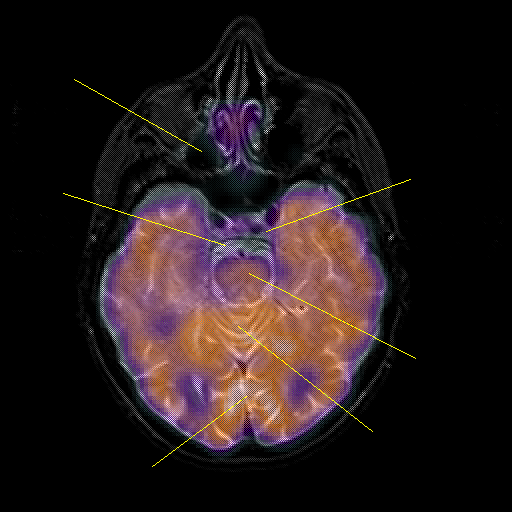

overlay : Slice 19

Slice 19

Pointers

Labeled